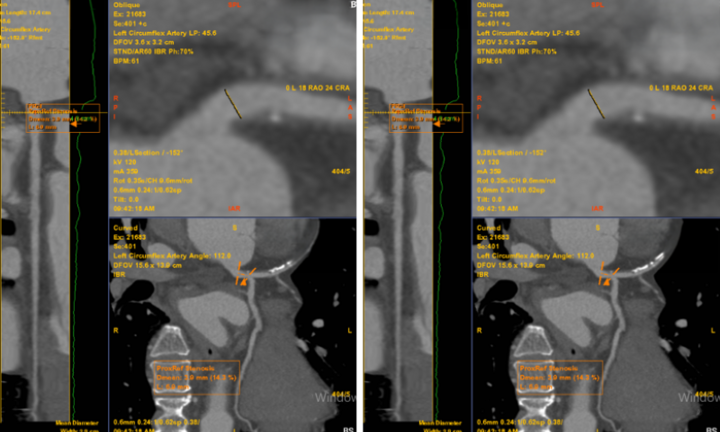

Đau ngực, mỗi cơn đau nhói kéo dài 5-10 phút, người đàn ông đến viện sàng lọc, chụp CT mạch vành 2560 lát cắt phát hiện bị hẹp mạch máu nuôi tim.